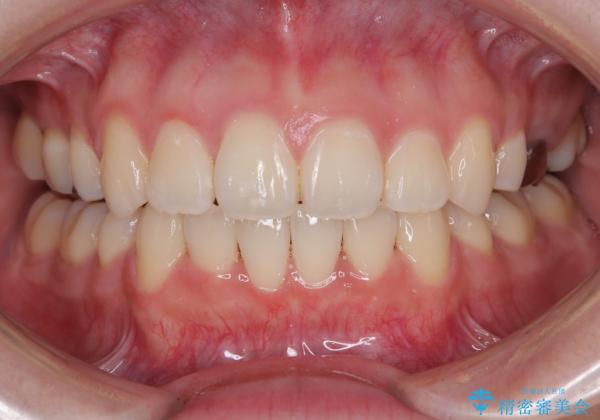

- 下の前歯のデコボコと、口元の突出感を改善したいと来院された患者様です。

突出感の強い上顎前歯をしっかりと後方移動させるため、上顎の裏側の補助装置(リンガルアーチ)とアンカースクリューを併用しています。

上下左右の第一小臼歯を抜歯して、目立ちにくいワイヤー装置で矯正を行いました。

上下の保定用マウスピースの他に、デコボコの強かった下顎前歯にはワイヤーで保定をしています。